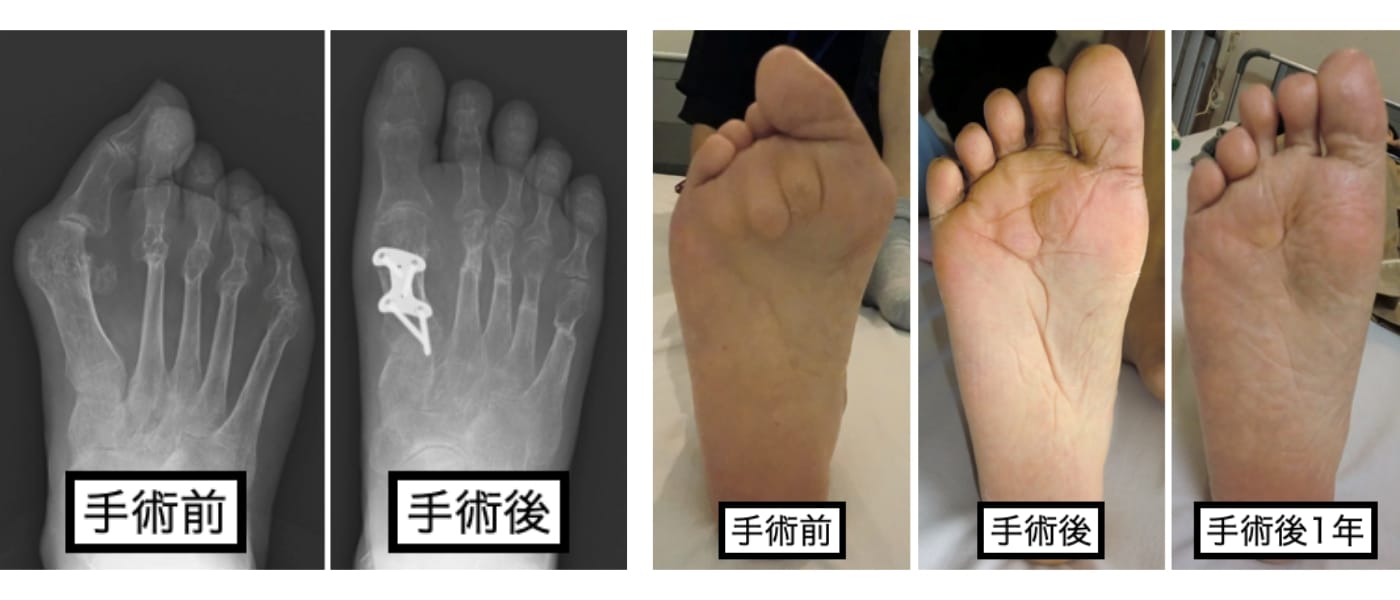

抗リウマチ治療により、疾患活動性が落ち着いている場合や足趾関節の破壊が高度でなければ、可能な限り関節温存型の足趾形成術を行なっています(下図)。

足趾関節を温存することで、足部の踏み返し運動の改善が期待できるため、歩容の改善も期待できます。また、中足骨頭を残す際に骨頭の配列も矯正するため、足底部の有痛性胼胝の自然軽快も期待できます(下図)。